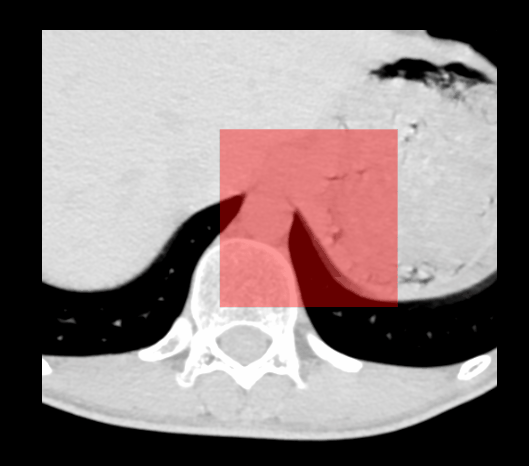

本文介绍如何使用 VTK 库中的 vtkImageMask 实现图像掩码功能,并提供了一个具体的 C++ 示例代码。该方法可以将指定区域从原始图像中突出显示出来,适用于医学影像等领域。

1、使用 vtkImageMask 实现。

优点:简单方便,mask与原始图像大小一致;

缺点:只支持单一掩码图像,无法实现多个掩码的编辑;